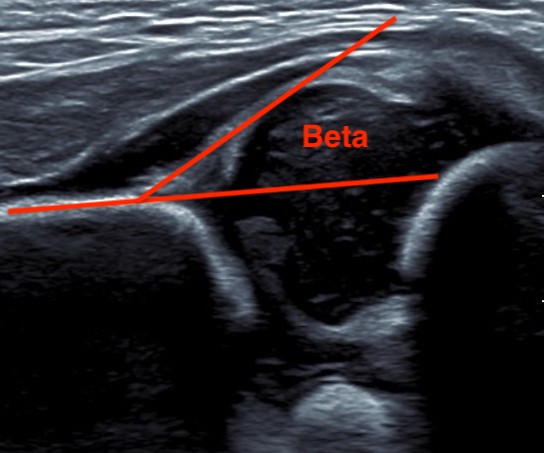

| Alpha Angle | Beta Angle | Dynamic |

|---|---|---|

|

Between ilium & cartilage roof / labrum

Normal < 60o |

Beta angle between ilium and cartilage roof / labrum